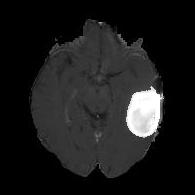

We first introduce a method for connecting the output of a CNN to an ACM, yielding a model for the precise delineation of lesions, to which we refer as Deep Active Lesion Segmentation (DALS) (Figure 4). We then go further to introduce a truly unified framework (Figure 5) that bridges the gap between ACMs and CNNs by leveraging a novel, automatically differentiable level-set ACM with trainable parameters that allows for back-propagation of gradients and can be end-to-end trained along with a backbone CNN from scratch, without any CNN pre-training. The ACM is initialized directly by the CNN and utilizes an energy functional that is locally-tunable by the backbone CNN, through 2D feature maps. Thus, our work overcomes the big hurdle of fully automating the powerful ACM approach to image segmentation. We have applied our proposed framework to the task of building segmentation in aerial images (Figure 6).

(a) Input image (b) DTAC Output (c) (d)